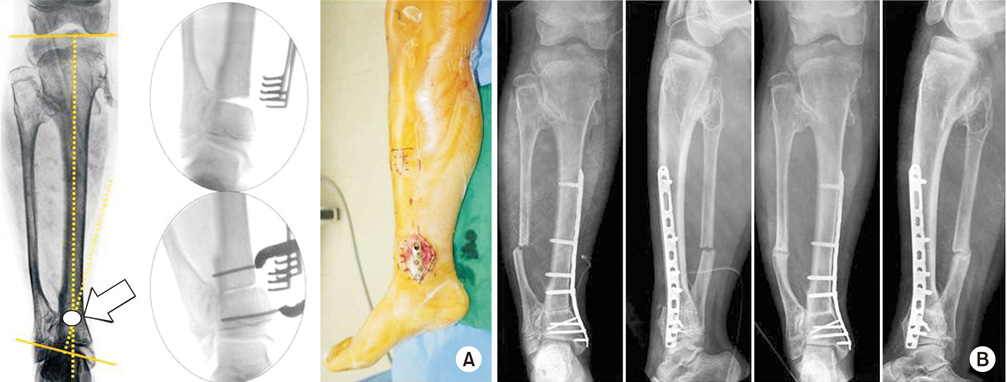

(A) In a 13-year-old male with valgus deformity due to osteochondroma, center of rotation of angulation was located at the distal tibia (arrow). We performed a medial close wedge osteotomy and restored the alignment by compressing the gap of osteotomy. The osteotomy site was fixed with minimally invasive plate osteosynthesis. (B) The anatomical alignment was recovered after operation. Six months later, bony union was completed.

Fig. 4 (A) In a 13-year-old male with valgus deformity due to osteochondroma, center of rotation of angulation was located at the distal tibia (arrow). We performed a medial close wedge osteotomy and restored the alignment by compressing the gap of osteotomy. The osteotomy site was fixed with minimally invasive plate osteosynthesis. (B) The anatomical alignment was recovered after operation. Six months later, bony union was completed.